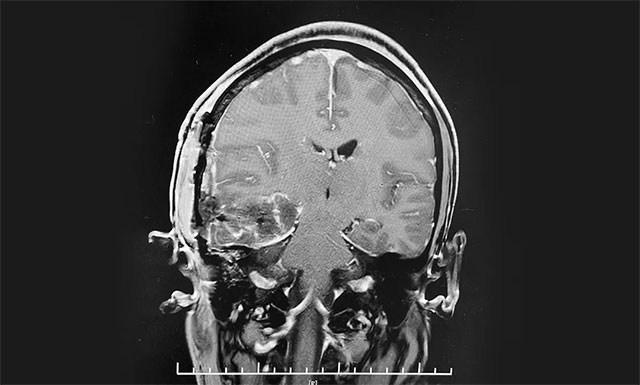

術(shù)中,在蔡司顯微鏡(雙熒光)下見右顳葉局部腦組織顏色較周圍略黃,自此處切開腦組織,見腦組織內(nèi)有黑灰色“腫物”,與周圍腦組織邊界清楚,切開腫物,見其內(nèi)有暗紅色血性液體,部分腫物機化樣。李士其教授在吳治群博士、黃秀夫醫(yī)生協(xié)助下,嚴(yán)格沿瘤腦邊界分離腫瘤,最終利用嫻熟的解剖和顯微技術(shù)將“血管瘤”順利切除,留取腫物送病理,并清除血腫。術(shù)前腦血管造影提示與病灶關(guān)聯(lián)的深部粗大靜脈獲得完整保留,有效避免了術(shù)后再出血,手術(shù)順利完成。

病理標(biāo)本檢測,確診為右顳葉海綿狀血管瘤。

▲ 術(shù)后MR顯示,“腫瘤”被切除